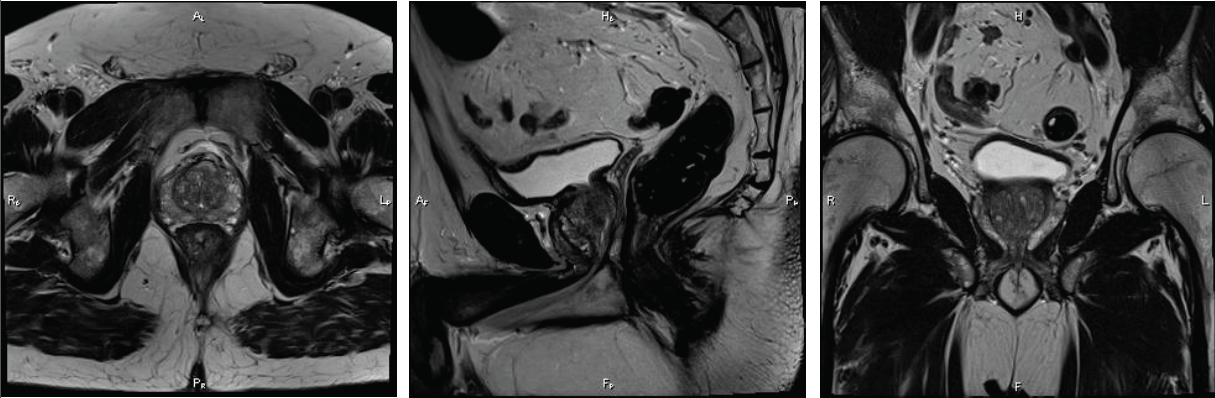

Für eine exakte Prostata MRT in Hamburg setzen wir auf eine multiparametrische MRT-Bildgebung mit einem 3 Tesla MRT. Multiparametrisch bedeutet, dass nicht nur die Form und Größe der Prostata erfasst wird, sondern auch Gewebscharakteristika erfasst werden. So kann unter anderem durch Zugabe eines Kontrastmittels auch die Durchblutung eines Areals analysiert werden. Auf diese Weise entstehen sehr detailreiche Aufnahmen, die Aufschlüsse über mögliche Karzinome etc. zulassen.

In manchen Fällen ist dies möglich. So wird eine Biopsie häufig in Folge eines erhöhten PSA-Werts angeordnet. Neben einem bösartigen Karzinom können jedoch auch eine vergrößerte Prostata oder eine Entzündung den PSA-Wert beeinflussen. In solchen Fällen wäre eine Biopsie also nicht erforderlich. Mit einer multiparametrischen Prostata MRT in Hamburg lässt sich gezielt ermitteln, ob ein Prostatakarzinom vorliegt. Dank der exakten Bildgebung können nachträglich noch erforderliche Biopsien zudem wesentlich präziser durchgeführt werden.